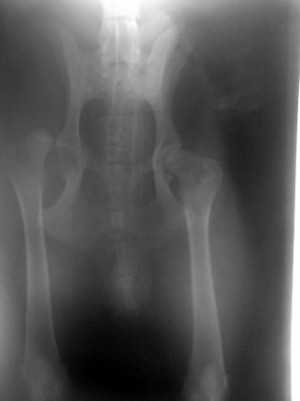

Beckenfaktur

Hüftgelenksluxation